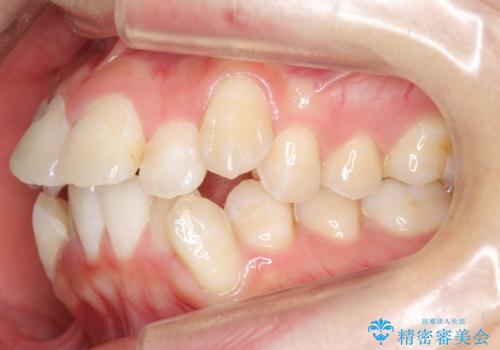

八重歯の治療 仕上がり重視で

- 八重歯を主訴に来院。

仕上がり重視とのことで、小臼歯を抜歯し、スタンダードな治療方法で仕上げています。